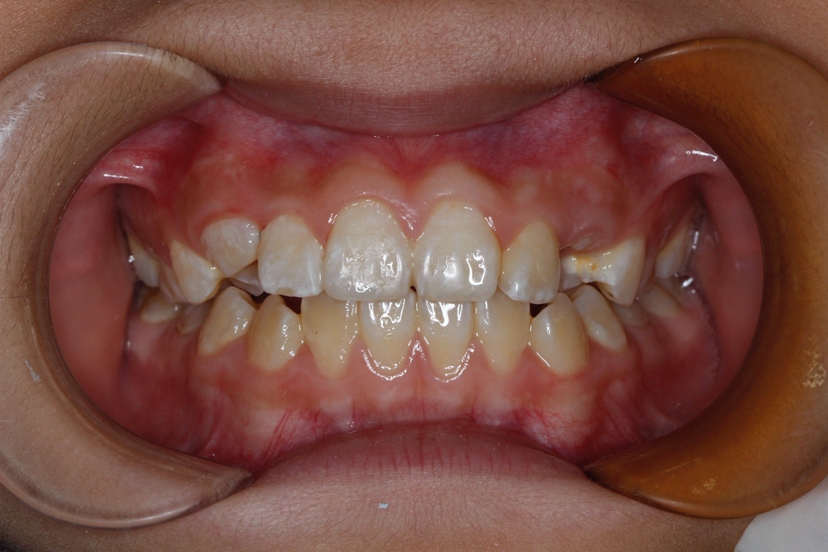

该患者年轻恒牙前牙外伤,切缘缺损,未露髓。根尖周无低密度影像。最终树脂修复,牙齿形态完善。后期定期观察。